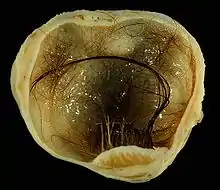

Immature (solid) teratoma

.jpg.webp)

Immature, or solid, teratomas are the most common type of ovarian germ cell tumor, making up 40–50% of cases. Teratomas are characterized by the presence of disorganized tissues arising from all three embryonic germ layers: ectoderm, mesoderm, and endoderm; immature teratomas also have undifferentiated stem cells that make them more malignant than mature teratomas (dermoid cysts). The different tissues are visible on gross pathology and often include bone, cartilage, hair, mucus, or sebum, but these tissues are not visible from the outside, which appears to be a solid mass with lobes and cysts. Histologically, they have large amounts of neuroectoderm organized into sheets and tubules along with glia; the amount of neural tissue determines the histologic grade. Immature teratomas usually only affect one ovary (10% co-occur with dermoid cysts) and usually metastasize throughout the peritoneum. They can also cause mature teratoma implants to grow throughout the abdomen in a disease called growing teratoma syndrome; these are usually benign but will continue to grow during chemotherapy, and often necessitate further surgery. Unlike mature teratomas, immature teratomas form many adhesions, making them less likely to cause ovarian torsion. There is no specific marker for immature teratomas, but carcinoembryonic antigen (CEA), CA-125, CA19-9, or AFP can sometimes indicate an immature teratoma.[33]

Stage I teratomas make up the majority (75%) of cases and have the best prognosis, with 98% of patients surviving five years; if a Stage I tumor is also grade 1, it can be treated with unilateral surgery only. Stage II though IV tumors make up the remaining quarter of cases and have a worse prognosis, with 73–88% of patients surviving five years.[33]

Mature teratoma (dermoid cyst)

Mature teratomas, or dermoid cysts, are rare tumors consisting of mostly benign tissue that develop after menopause. The tumors consist of disorganized tissue with nodules of malignant tissue, which can be of various types. The most common malignancy is squamous cell carcinoma, but adenocarcinoma, basal-cell carcinoma, carcinoid tumor, neuroectodermal tumor, malignant melanoma, sarcoma, sebaceous tumor, and struma ovarii can also be part of the dermoid cyst. They are treated with surgery and adjuvant platinum chemotherapy or radiation.[33]